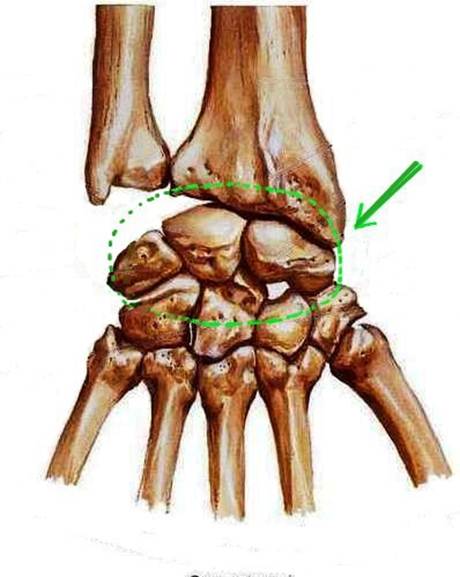

S: Числом 10 обозначена os trapezium (латинский язык).

S: Цифрой 8 обозначена os capitatum

S: Числом 12 обозначена os scaphoideum

S: Числом 13 обозначена os triquetrum

S: Цифра 3 указывает на phalanx proximalis

S: Цифра 2 указывает на phalanx media

S: Цифра 1 указывает на phalanx distalis